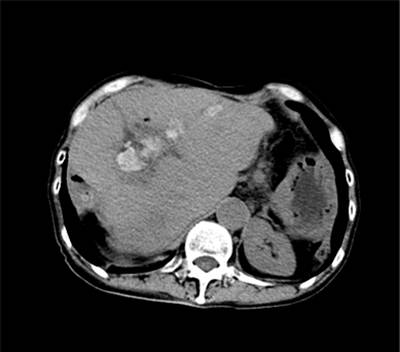

患者,女, 60岁。从记事起就经常出现寒战、发烧、肚子痛。 30岁时在当地医院就医,确诊为肝内胆管结石、急性胆管炎、胆囊结石,接受了胆囊切除手术和胆管取石手术。之后周某因肝内胆管结石复发,先后行4次开刀手术,中上腹手术切口瘢痕纵横交错。近期,患者复查发现肝内胆管结石再次复发。患者非常惧怕再次开刀,采用保守消炎治疗,半年期间,反复出现寒战、发烧、腹痛,皮肤巩膜黄疸由浅变深。入院后完善腹部CT检查,在肝门胆肠吻合口附近和左边肝内胆管发现多发结石,导致肝内胆管明显扩张。患者不愿意再次开刀手术,选择行经皮经肝胆道镜碎石取石术(PTCSL)。我们在患者的肚子上打了个5mm的小孔,通过经皮经肝胆道镜碎石取石术,取尽患者肝内胆管结石。患者术后顺利康复出院,目前患者已经恢复了正常的工作和生活。

术前CT提示肝内胆管多发结石